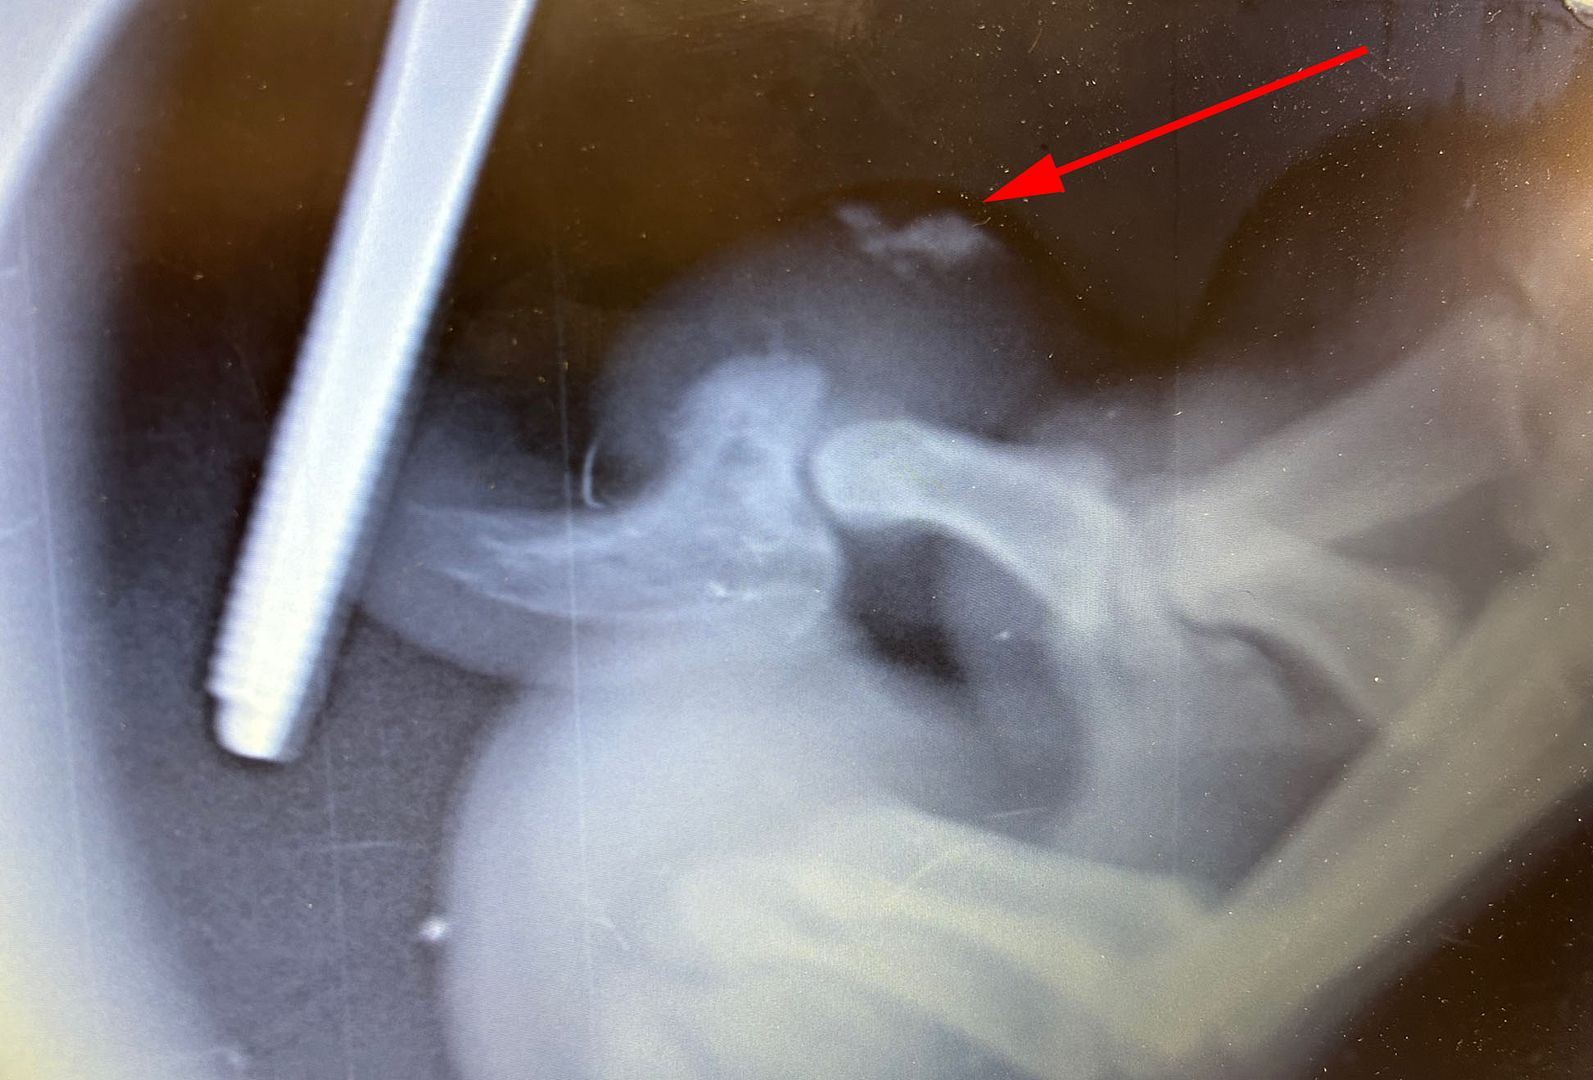

She had surgery on one of her foot pads to remove debris - here are the x-rays:

She had an intermittent limp that just wouldn't go away, and although there was a small puncture wound on her pad, I couldn't find anything in it (I often remove partially imbedded rocks from her pads). The vet didn't either the first time he looked at it, but when it didn't go away we took he back and they did the x-rays.

Yes. They were able to use dental x-rays to quickly see the issue...